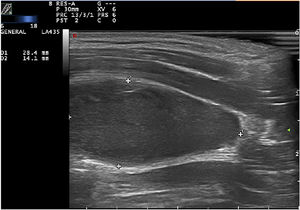

Ante las dudas diagnósticas, se decidió realizar una ecografía cutánea con sonda lineal a una frecuencia de 15-18MHz con equipo Esaote Mylab en la que se apreció una estructura hipoecoica y ovalada, de bordes bien definidos, de 2,8×1,5×1,4cm, con eje mayor en sentido longitudinal, localizada por debajo del músculo esternocleidomastoideo. El modo Doppler color mostró una ausencia de vascularización intralesional, con presencia de vascularización periférica (figs. 2 y 3). Los hallazgos ecográficos fueron compatibles con un hematoma intramuscular.

Desde el punto de vista ecográfico, el diagnóstico diferencial de nuestra paciente incluyó el lipoma, las adenopatías y la trombosis. Los lipomas presentan una ecogenicidad variable y en ocasiones un bandeado hiperecogénico característico. Tienden a localizarse en el tejido celular subcutáneo y sus límites a menudo no están claramente delimitados. Las adenopatías suelen presentar morfología ovalada, centro hiperecoico y halo hipoecogénico periférico, aunque en estados inflamatorios se puede observar un aumento de volumen y vascularización, si bien conservan su morfología y ecoestructura. Las trombosis son lesiones habitualmente hiperecogénicas, en el interior de los vasos, que pueden presentar vascularización periférica (recanalización). El hematoma se manifiesta ecográficamente como una imagen hipoecoica o anecoica, sin flujo sanguíneo en su interior, pero con vascularización dópler periférica6. Esta última descripción coincidió con los hallazgos ecográficos de nuestra paciente.